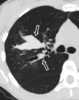

Mucoid impaction in bronchus